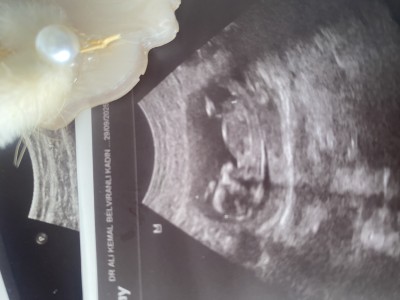

Cinsiyet tahmini yaparmısınız 🤍

Gebelik haftası 15 hafta 4 gun

Erkek hissettim